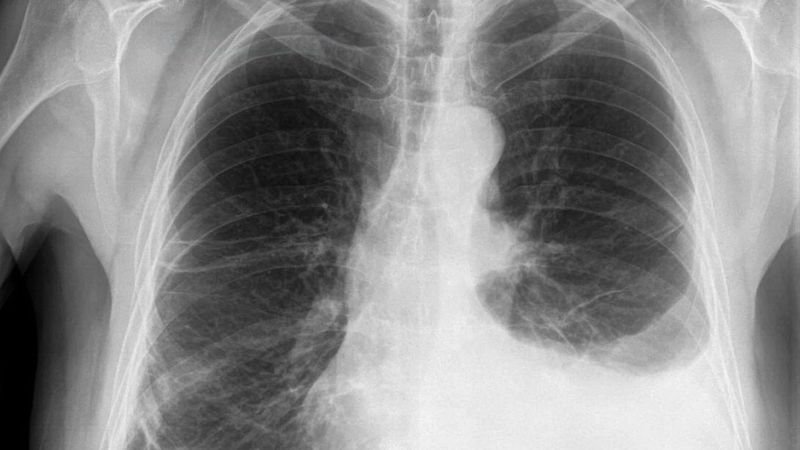

Imaging Tests

X-ray, ultrasound, or CT scan confirmation.